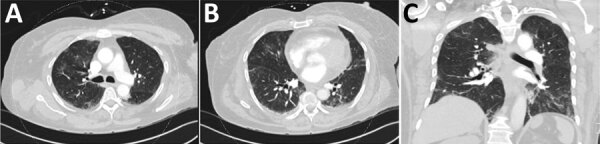

Description:We report 2 fatal exacerbations of systemic capillary leak syndrome (SCLS), also known as Clarkson disease, associated with coronavirus disease (COVID-19) in the United States. One patient carried an established diagnosis of SCLS and the other sought treatment for new-onset hypotensive shock, hemoconcentration, and anasarca, classic symptoms indicative of an SCLS flare. Both patients had only mild-to-moderate symptoms of COVID-19. This clinical picture suggests that these patients succumbed to complications of SCLS induced by infection with severe acute respiratory syndrome coronavirus 2. Persons with known or suspected SCLS may be at increased risk for developing a disease flare in the setting of mild-to-moderate COVID-19 infection.